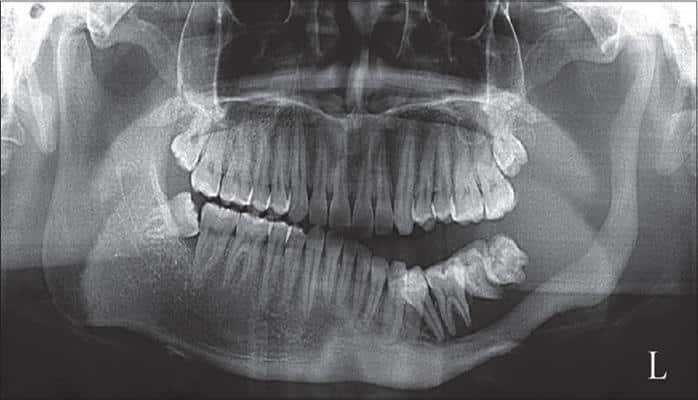

С 1954 года в истории медицины было зафиксировано всего 64 случая синдрома исчезающих костей и большинство из них поражали кости рук. В сети можно найти еще более редкие аномалии, когда синдром поражал кости черепа, в том числе нижнюю челюсть.